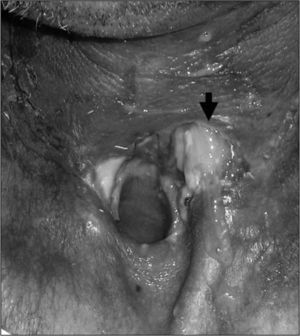

ResultadosObservamos que la extensión de la cirugía a la faringe es el único factor asociado significativamente (p=0,04) a la aparición de fístulas en nuestro medio (odds ratio [OR] = 2,83). La asociación de radioterapia previa y vaciamientos cervicales muestra una tendencia importante (OR = 3,2), no significativa (p=0,099). Otros factores como la edad del paciente, la radioterapia previa, los vaciamientos cervicales, la traqueotomía previa o la hemoglobina postoperatoria no se asocian estadísticamente a la aparición de esta complicación. La mayoría de las fístulas se cierran con medidas conservadoras (72,7 %), pero en pacientes irradiados previamente requieren reparación quirúrgica con mayor frecuencia que en los no irradiados (p <0,01).

ConclusionesEn nuestro medio el factor más asociado a la aparición de fístulas tras laringectomía es la extensión de la cirugía a la faringe. Las fístulas en pacientes irradiados tienen menor tendencia a la reparación conservadora y requieren cirugías más agresivas para solucionarlas.

ResultsThe only risk factor with statistical significance (P=.04) for the onset of fistulae in our setting is the extension of the surgery to the pharynx (OR=2.83). The association of prior radiotherapy and concurrent neck dissection displayed a notable trend (OR=0.32) but without significance (P=.099). Patient age, prior radiotherapy, concurrent neck dissection, prior tracheotomy and post-operative haemoglobin level did not predispose to this complication in our study. Non-surgical closure of the pharyngocutaneous fistula was achieved in most cases (72.7 %) but patients who had pre-operative radiotherapy required surgical closure more frequently (P<.01) than those not irradiated.

ConclusionsAt our centre the main risk factor associated with post-laryngectomy fistulae is the extension of surgery to the pharynx. In previously-irradiated patients, fistulae have a lower incidence of non-surgical closure and require more aggressive surgery to resolve them.